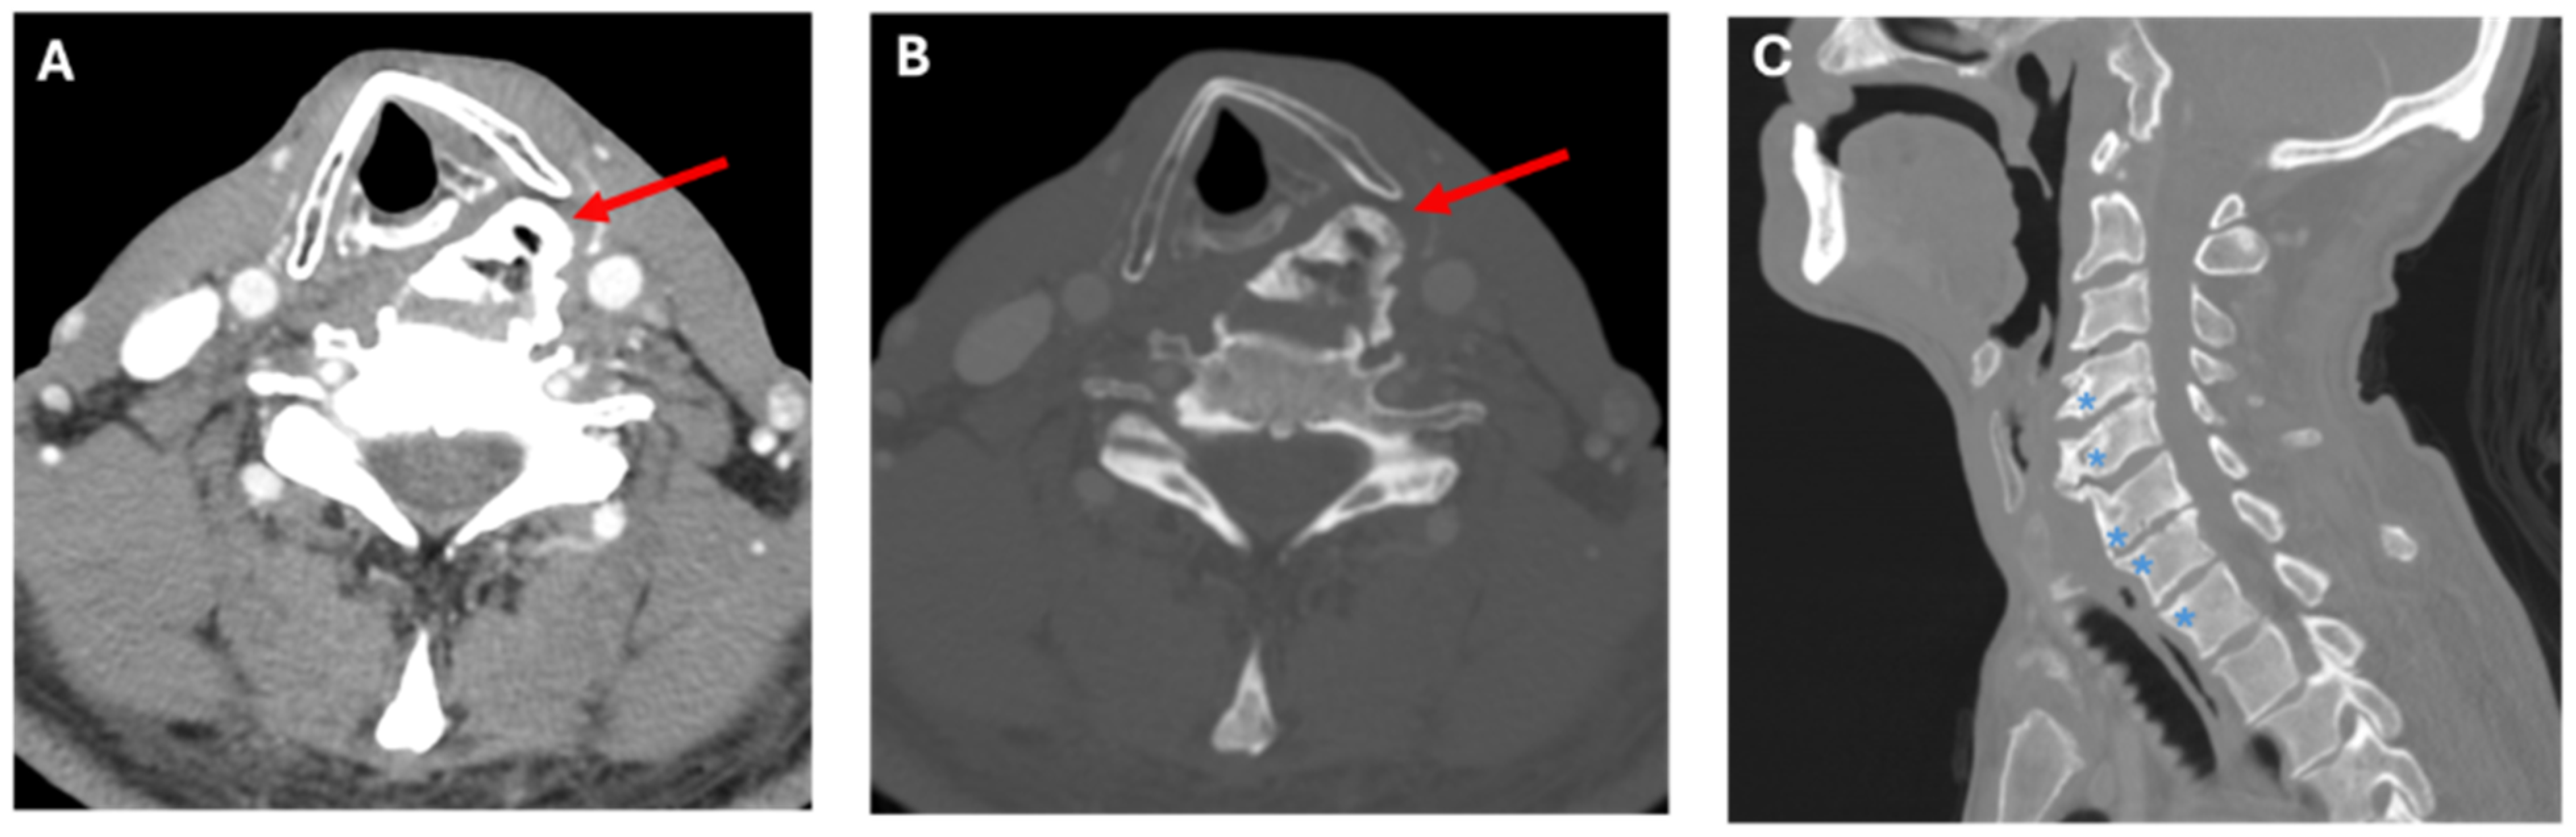

Figure 2.

Computed Tomography images for Case A. CT images in axial soft tissue (A), axial bone window (B), and sagittal bone window (C) reconstructions. Images demonstrate a large left endplate osteophyte (red arrow), which projects into the left cricothyroid joint in a patient with left vocal cord palsy. The sagittal image shows multi-level bulky endplate osteophyte formation (blue asterisk), without substantial disc degeneration, in keeping with findings of DISH.

The patient’s voice handicap index (VHI) score was 28/40, and his singing voice handicap index was 30/40. Strobovideolaryngoscopy found moderate paresis of the left vocal fold with glottic insufficiency as well as pyriform sinus pooling (Figure 1A,B). CT imaging found numerous radiographic features consistent with a diagnosis of DISH and showed large anteriorly projecting osteophytes in the cervical spine, eccentric to the left (Figure 2A–C). In particular, a large osteophyte extended anteriorly to the left at C5–6, towards the larynx, along the posterior aspect of the left thyroid cartilage, with rightward deviation of the laryngeal structures and hypopharynx (Figure 2A–C). Flexible laryngoscopy with injection augmentation of the left vocal fold with carboxymethylcellulose gel was performed for symptomatic relief and a referral to a spine specialist was made for DISH management. The patient tolerated the injection augmentation well, without complication, and reported complete symptom resolution at subsequent follow-up. The patient did not elect for further management of his osteophytes at this time.